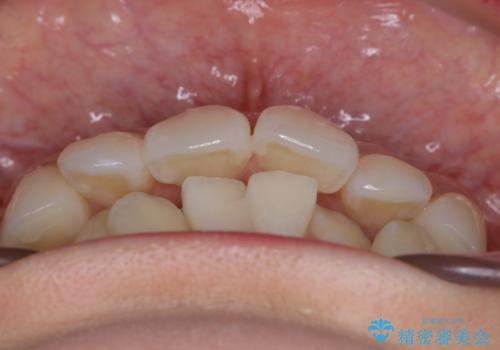

- 治療計画

- 歯のガタつきと出っ歯感を治したいとの主訴でご来院され、ハーフリンガル装置を希望なさったため、検査を行ったうえで上下左右4番目の歯を抜歯し歯列を内側に引っ込めつつ叢生の改善を行うこととなりました。

ハーフリンガルとは上顎を裏側、下顎を表側のワイヤー装置で治療する場合をいいます。

フルリンガル(上下とも裏側)で治療するよりも費用が抑えられ、治療期間も伸びにくい傾向にあります。また、下顎の舌側に装置がないおかげで口内炎や発音障害もフルリンガルに比べて少ないとされています。